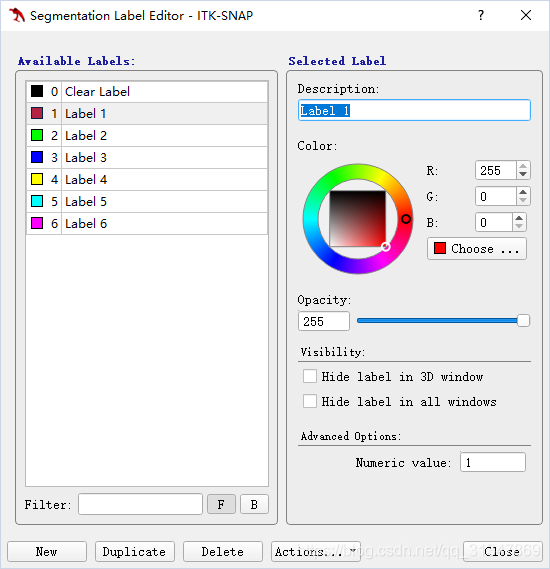

标签是 0 ~ 255 的数值,每个标签有自己的名字和显示设置(比如用什么颜色),其中 0 默认为每一个无标签的像素分配,名称为 ”Clear“,表示该像素未分配标签。

创建标签

修改 label:Segmentation -> Label Editor...

在 Description 处可修改当前 label 的名称,在 color 处可修改 label 的颜色,点击 New 可以新建 label,Opacity(不透明度):在 3D 分割中,如果有一个结构阻挡了分割的结构,可以使标签变得部分透明 ,Visibility:隐藏标签

需要创建自己的 label,只需要在 label editor 中改变已存在的 label 或新建 label

保存自己的 label 设置,选择导出即可